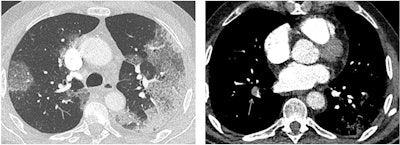

Revel also noted the risk of cytokine release syndrome in some patients, as well as a risk of pulmonary embolism in some patients (between 23% and 30% of those admitted to the intensive care unit with elevated D-dimer values), she told session attendees. Yet other SARS-CoV-2-infected patients develop microvascular injury syndrome involving at least the lungs and skin, which explains "why COVID-19 has clinical features distinct from typical ARDS [acute respiratory distress syndrome] with profound hypoexemia contrasting with relatively well-preserved lung mechanics," she said.